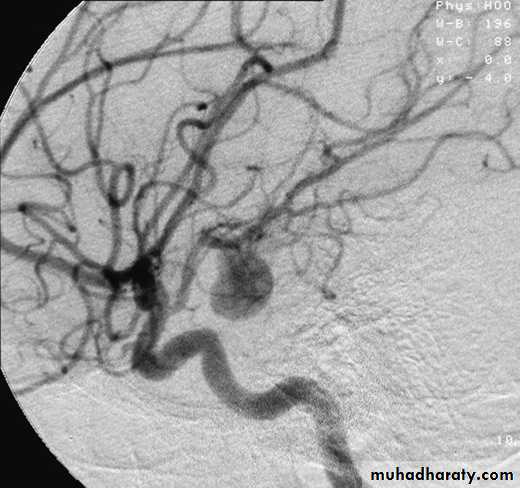

Saccular aneurysms

Fusiform aneurysms